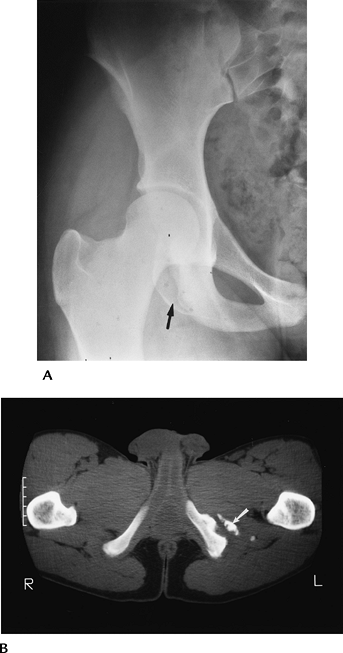

![]() |

FIGURE 4-2 (A) AP radiograph of the hip demonstrating an ischial avulsion fracture. (B) CT image of an old ischial avulsion fracture.